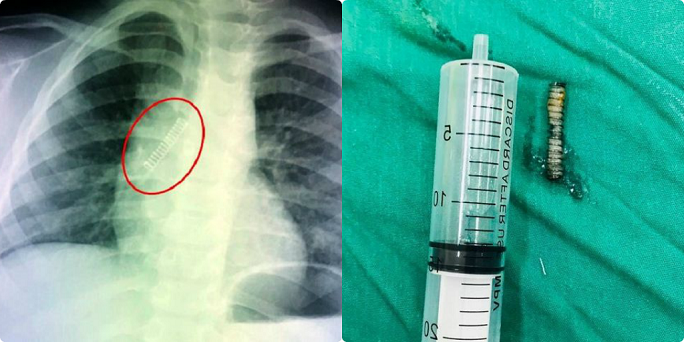

Mở quả trứng đồ chơi, bé trai bị lò xo bắn vào phổi

Vừa mở quả trứng đồ chơi, một cháu bé 4 tuổi ở TPHCM bất ngờ bị chiếc lò xo bắn vào miệng ho sặc sụa, tím tái phải nhập viện cấp cứu.